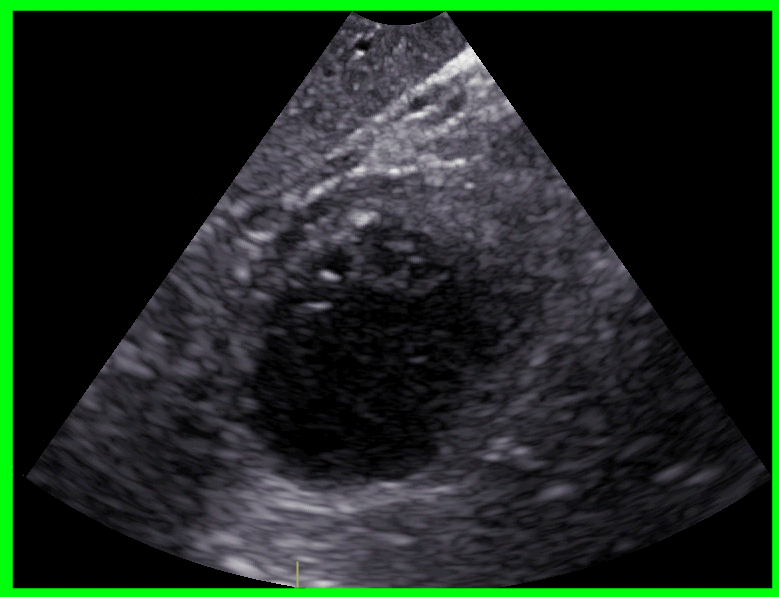

包围-盒区:

133 25 736 635剪切并保存最终图像: